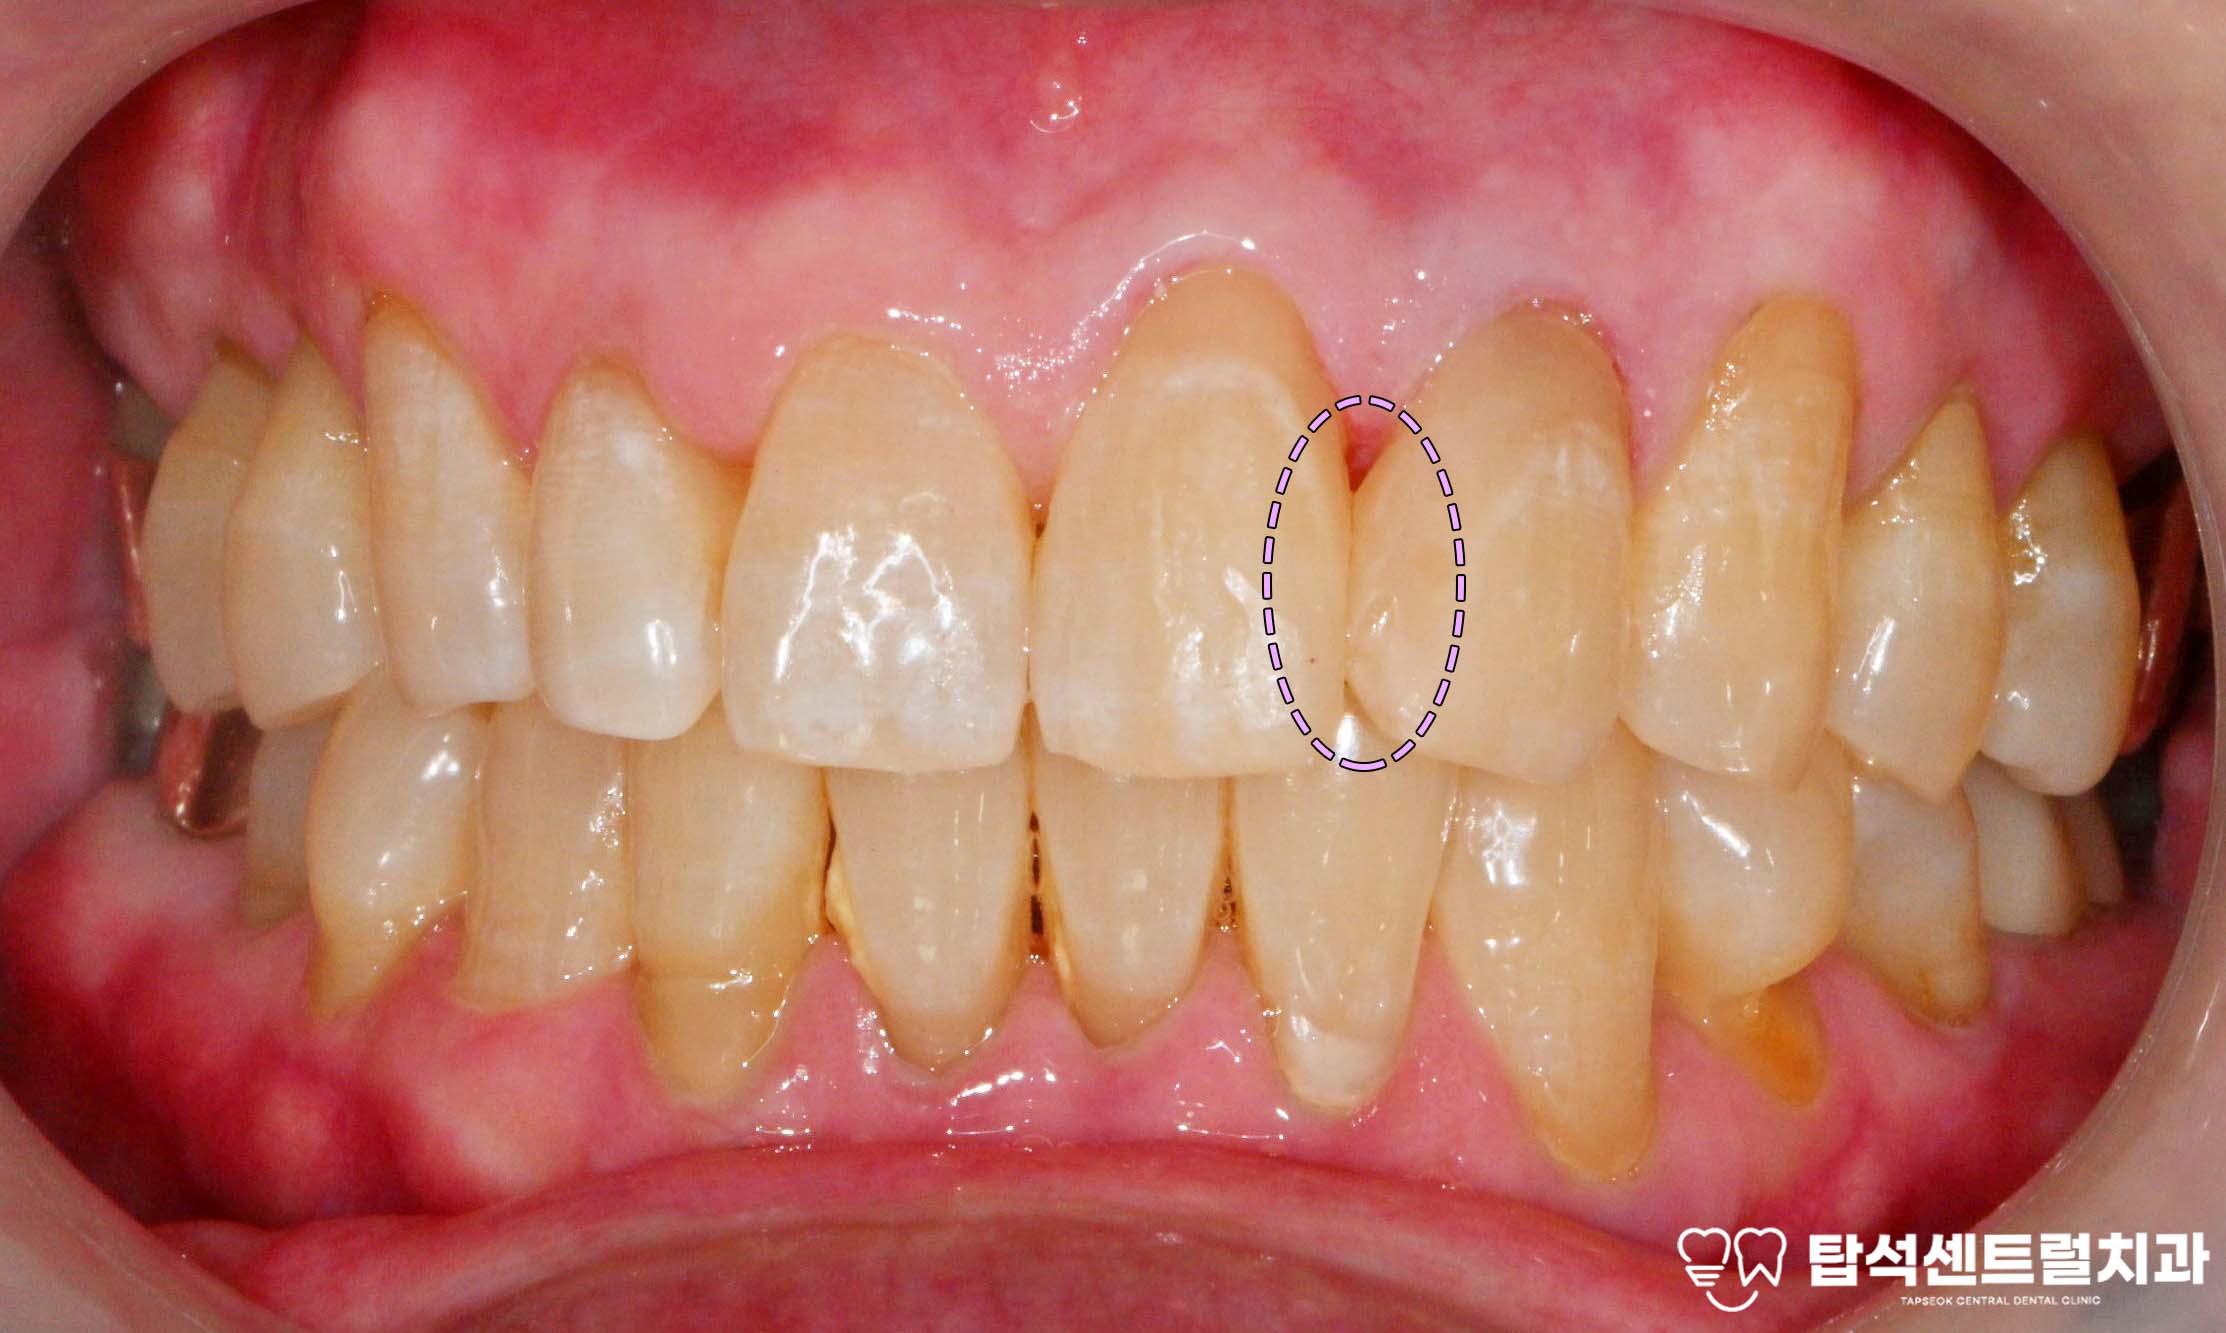

벌어진 앞니 사이 공간, 어떻게 개선할 수 있을까

벌어진 앞니 사이에 공간이 있으면

벌어진 공간 사이로 음식물이 끼면

잇몸에 자극을 주어

염증이 발생하는 상황도

생각해볼 수 있습니다.

벌어진 앞니 부위 결과와 관리 방법 소개

벌어진 윗니 사이 부분을 메운 후에는

자연스러운 형태로

회복되는 것을 확인할 수 있습니다.

벌어진 앞니 부위를 방치하면?

발음 장애가 지속되고

식사할 때 불편함이 계속되어

생활의 질이 저하됩니다.

치아 사이에 음식물이 자주 끼어

잇몸 염증과 충치가 발생할

위험이 높아지며,

인접치의 기울어짐 같은

2차 문제가 생길 수 있습니다.